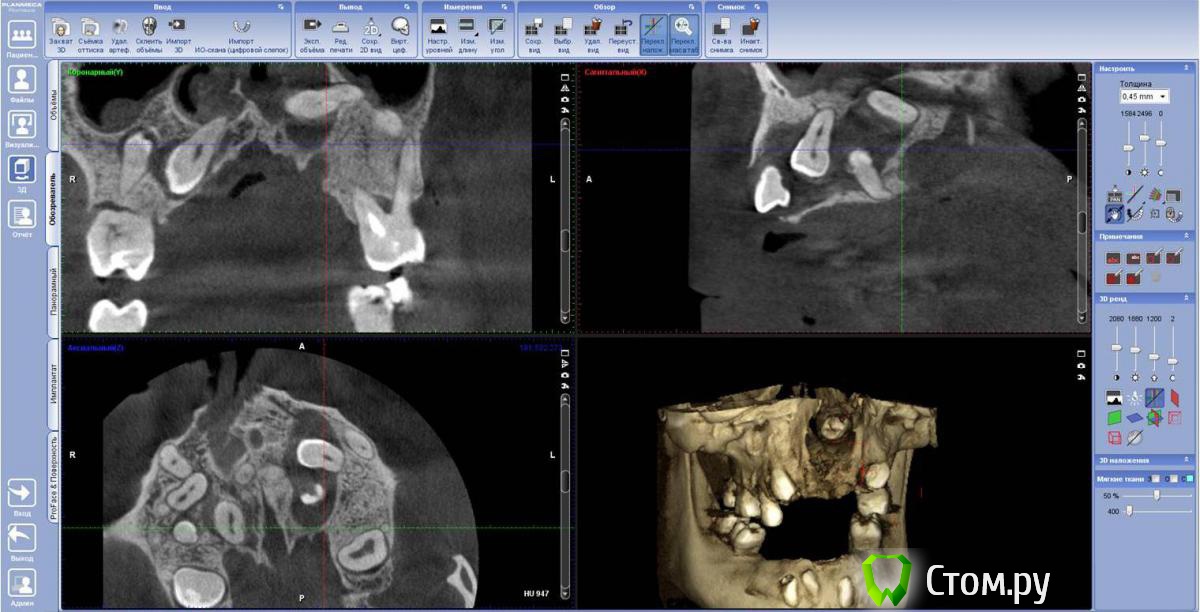

FBR Опубликовано 28 января, 2014 Поделиться Опубликовано 28 января, 2014 (изменено) Планируется протезирование на имплантатах ( в перспективе). Оперировать 1 этап (удаление зубов), планируем с ЛОРом. Изменено 28 января, 2014 пользователем FBR Ссылка на комментарий

diesel87 Опубликовано 28 января, 2014 Поделиться Опубликовано 28 января, 2014 Вторым этапом планируется костная пластика? Ссылка на комментарий

SergioS Опубликовано 28 января, 2014 Поделиться Опубликовано 28 января, 2014 Тут наверное в 2 этапа только пластика будет. Ссылка на комментарий

FBR Опубликовано 29 января, 2014 Автор Поделиться Опубликовано 29 января, 2014 Красота. А сколько лет пациенту?34 года. Пока по плану с лором определяемся. Думаю убрать слева зубы с минимальной травмой кости. 25 лежит в носу и частично в кисте. Ссылка на комментарий